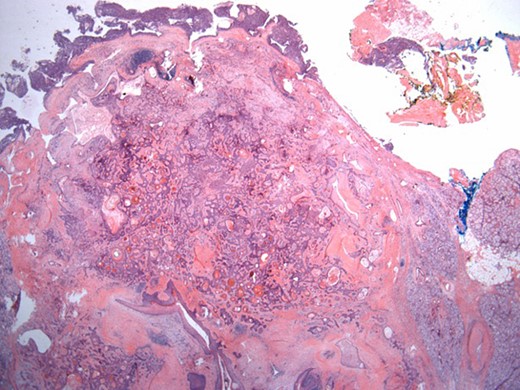

The surgical specimen showed a well-delineated submucosal nodule of 1.7 cm in the greatest diameter, without ulceration. Microscopically, this lesion appeared well defined with a central canal lined by keratinizing squamous epithelium without atypia (Fig. 2). In addition, we found confluent squamous foci with keratinizing centers (Fig. 3). The stroma was mostly fibrous, with occasional adipose and myxoid tissue. Only in the periphery of the lesion did we see a thin layer of normal ductal structures, highlighted by epithelial membrane antigen (EMA) positivity of the luminal cells, with immunochemistry studies (Fig. 4), whereas the other cellular component consisted of myoepithelial cells, highlighted by smooth muscle actin (SMA) and S100 protein (Fig. 5). No mucous secreting cell could be found. Keratin 5/6 and 903 were all positive for the whole specimen. The above-mentioned histopathologic findings helped to conclude the diagnosis of a PA with extensive squamous metaplasia. Margins were negative.

Well-circumscribed tumor on low power view. Hematoxylin and eosin (H&E ×25).